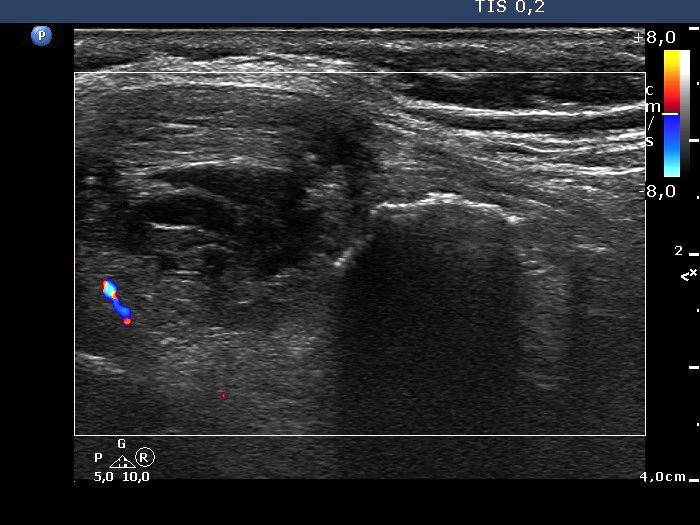

The composition of the nodule - case 653 (ultrasonographic picture 9)

Lower part of the left lobe, longitudinal scan, color Doppler mode. The nodule with eggshell calcification has no vascularization.